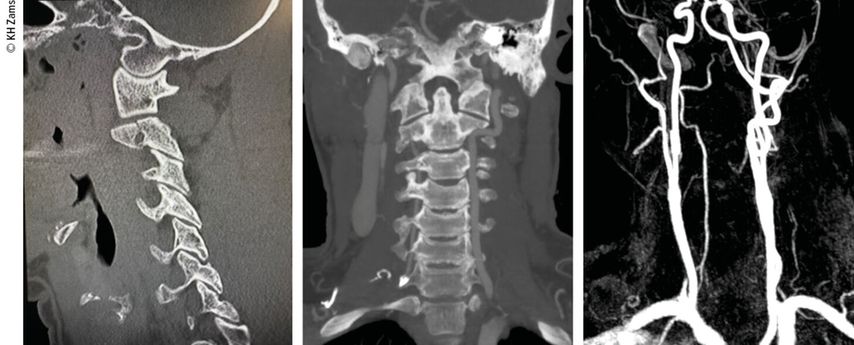

Abb. 4: Mann, 28a, Z.n. Schisturz; instabile Teardrop-Verletzung mit Dissektion A. vertebralis l.; Zervikobrachialgie mit Dysästhesie C6, mehrere kleine embolische Infarkte vertebrobasilär mit Koordinationsstörung; OP + Heparintherapie initial, anschließend APT